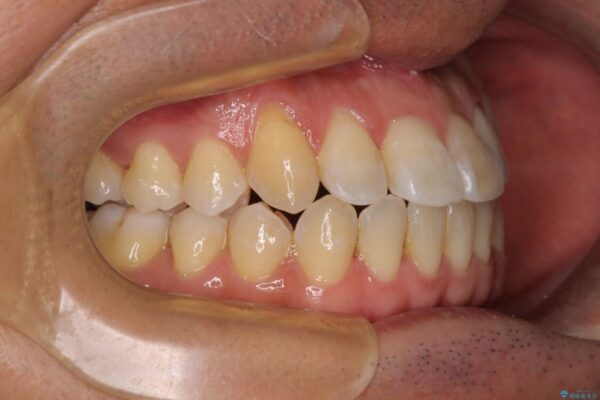

治療前

• 左右の八重歯が気になる ワイヤー装置での咬み合わせ改善 治療前画像